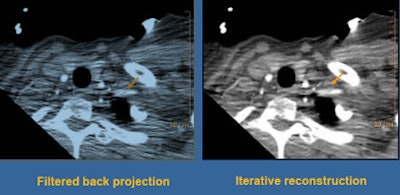

![]() |

| Photon starvation in the shoulder region was even more pronounced when the mAs and kV were reduced in the second study; fortunately, iterative reconstruction brought out a large amount of image detail. |

Using iterative reconstruction, "we cleaned things up a little bit through the body," Halliburton said. "What's impressive is the way we were able to clean things up through the shoulders. I think the use of iterative reconstruction for these really low-dose techniques is enabling us to deal with the shoulder issue."